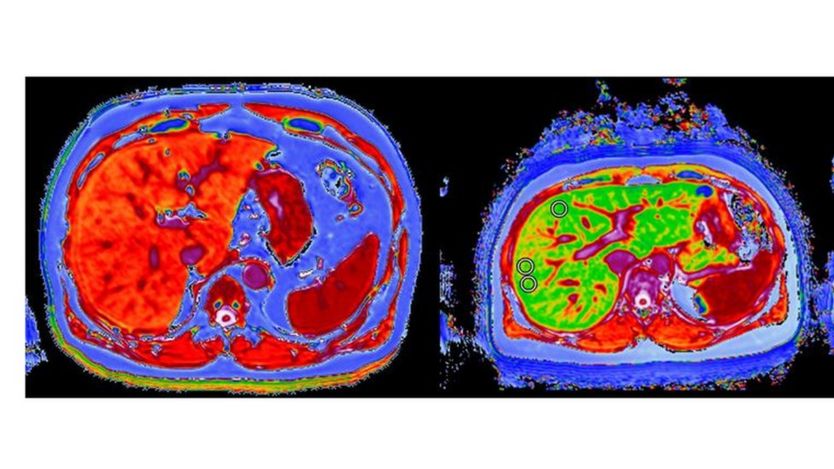

They were made possible by an innovative software analysis tool called LiverMultiScan, developed by Perspectum Diagnositics, a spin-out company from the University of Oxford.

The software tool can be used in any MRI scanner but is not yet in routine clinical practice.

David Breen, associate professor of radiology at University Hospital Southampton believes it could reduce the need for biopsies.

He said: "The scan gives a map of the entire liver as opposed to a needle-core biopsy which samples just one area and can be unpleasant.